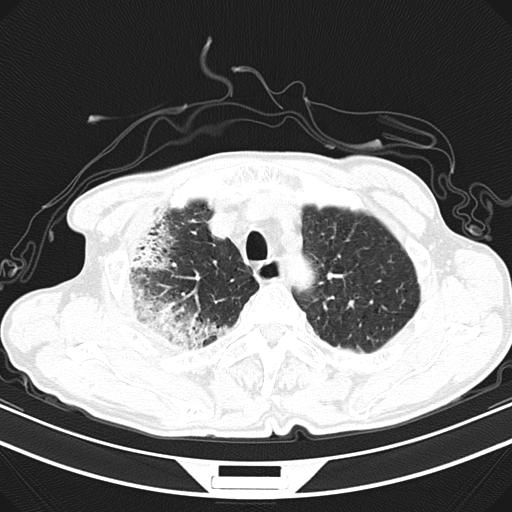

抗炎治疗10天后复查

抗炎治疗10天后复查:右上肺模糊阴影明显减少。

右肺感染性病变(右肺上叶肺脓肿?);建议:抗炎治疗后复查。